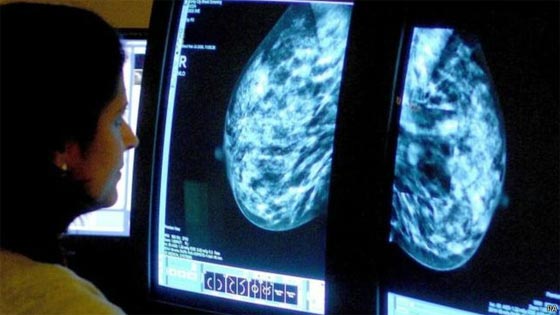

يعتبر تحسن وسائل الفحص من أسباب تعافي مرضى السرطان أو بقائهم على قيد الحياة لفترات أطول.